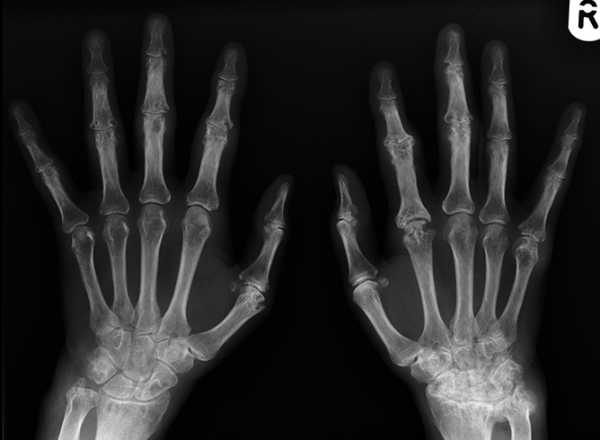

Для определения болезни используется комплекс мер. Сюда включают рентген для выявления костных наростов, уменьшения просвета щели между суставами, уплощении и деформации хрящей, разрушений костной ткани.

МРТ и УЗИ позволяет сделать более глубокое обследование состояния связок, сухожилий и нервных волокон. Лабораторные анализы (в т.ч. ревматоидный фактор) крови выявляют наличие воспалительного процесса.

В большинстве случаев это системное воспалительное заболевание начинается с болей в кистях рук, а именно в суставах у основания пальцев и лучезапястных сочленениях. Поражение симметричное, боли беспокоят больше в утренние часы, сочетаясь со скованностью движений. Также характерен стойкий отек, горячие кожные покровы. На более поздней стадии на кистях появляются плотные ревматоидные узелки, деформации пальцев по типу «лебединой шеи», «бутоньерки». Лечение ревматоидного артрита заключается в назначении базисных препаратов (метотрексат), гормонов (преднизолон), противовоспалительных средств и применении местной терапии (физиопроцедуры, ЛФК, массаж).

С помощью рентгена доктор поставит точный диагноз.Если у человека крутит и болит левая кисть либо правая, важно выяснить, из-за чего появляются такие признаки. При механических повреждениях конечности лечением проблемы будет заниматься травматолог и хирург. Если в организме прогрессируют дегенеративно-дистрофические патологии, справиться с проблемой поможет ревматолог. При неврологических повреждениях стоит обратиться к неврологу. При подозрении на системные нарушения нужно посетить эндокринолога, терапевта, кардиолога. А также стоит пройти ряд инструментальных диагностических процедур:

- рентгенографию;